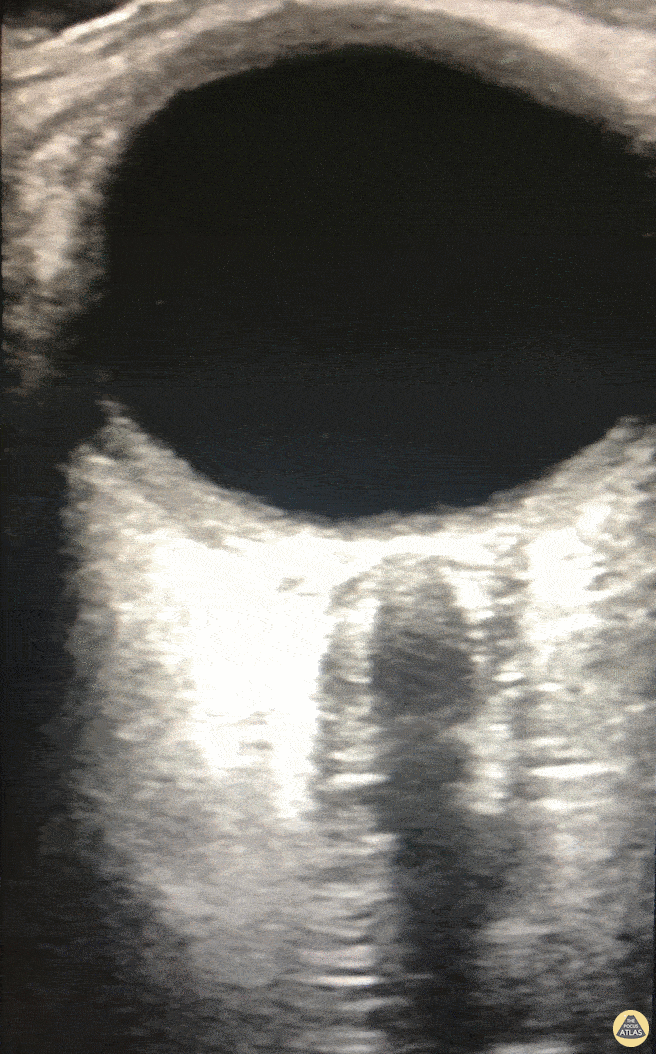

We used OSND to evaluate a patient with COVID-19 encephalitis and found evidence of increased intracranial pressure (ICP). Note, due to the high frequency probe used, we were able to appreciate fine detail including two hypoechoic boarders at each lateral edge of the optic nerve. It is the most lateral outer edge/ hypoechoic structure that represents the optic nerve sheath. Eric M. Siegal, MD, SFHM, FCCM Aurora Critical Care Service; Milwaukee, WI Adjunct Clinical Professor of Medicine University of Wisconsin School of Medicine and Public Health